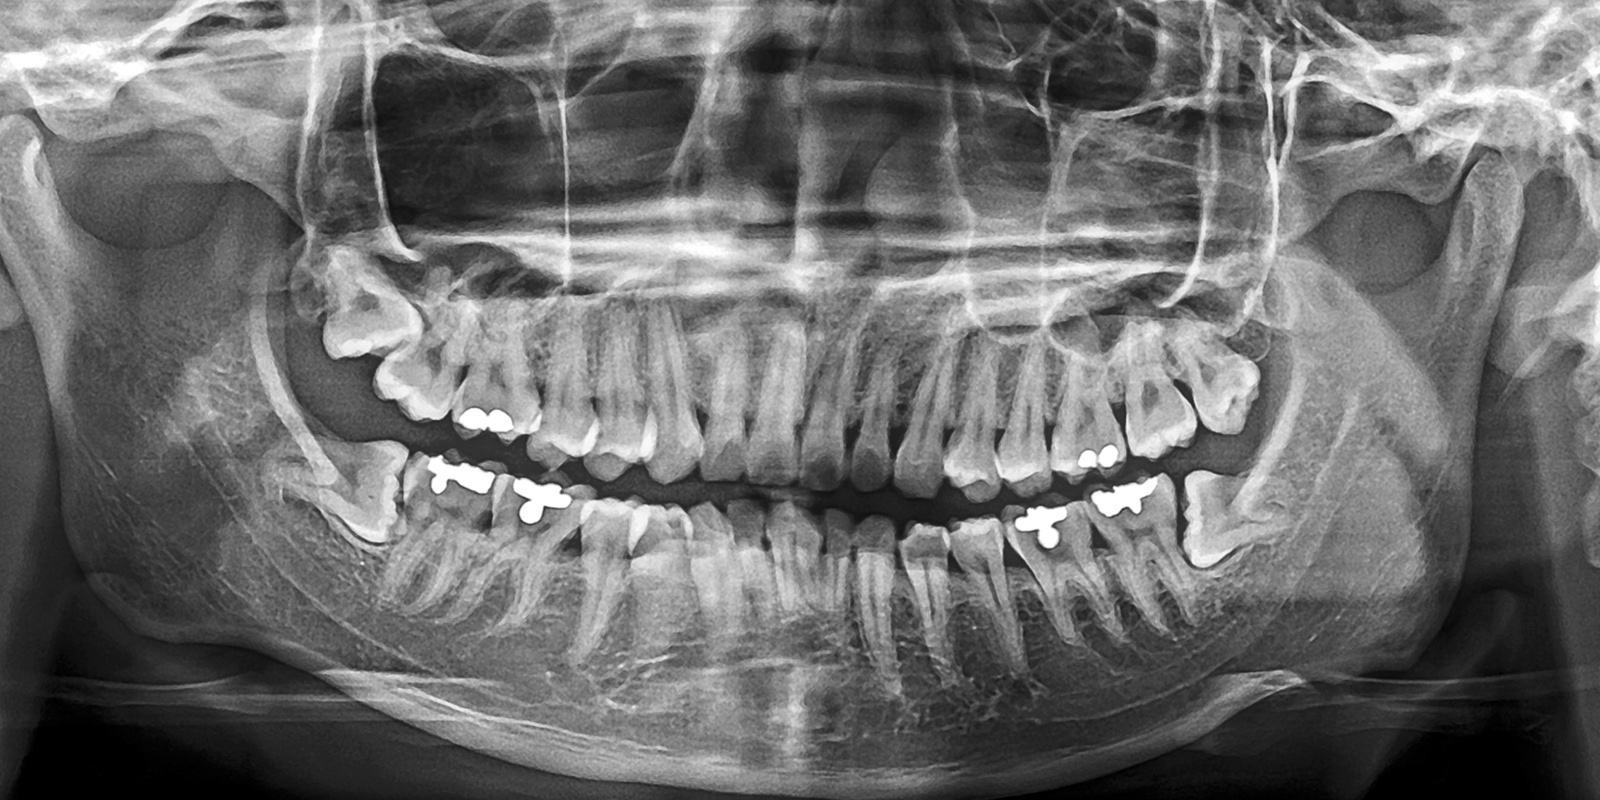

パノラマレントゲン

お口全体を1枚の画像で撮影できる、広範囲のレントゲン写真です。親知らずの位置や向き、周囲の歯との関係がひと目でわかります。

特に下あごの親知らずは、下歯槽神経という大事な神経の近くにあることが多く、抜歯による神経損傷のリスク評価が非常に重要です。

パノラマ撮影により、神経との距離や重なり具合を事前に確認できます。